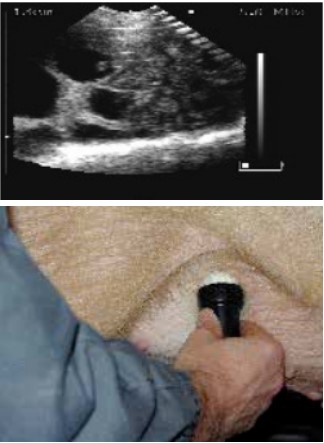

扫描配种第24天的母猪,大的胚胎囊可以很容易的看到。

Scans day 24. Large embryos bladders which are easy to see.

位置1的超声波图像.

Ultrasound image position 1.

扫描仪的探头涂上耦合剂后置于腹股沟部。

The scanner head is applied gel and is placed in the groin.

缓慢地移动探头,直至出现胚胎清晰的图像。

lowly move the scanner head around until there is a clear picture of the fetus.